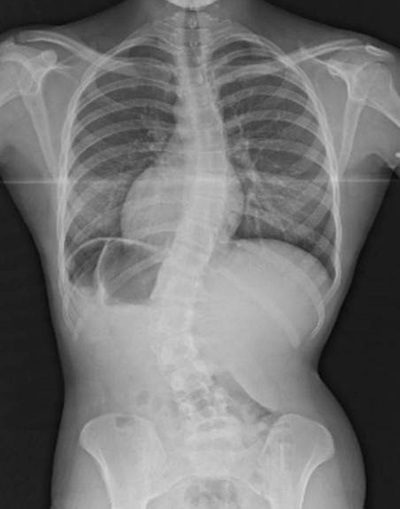

Ảnh chụp X-quang cho thấy đoạn cột sống bị xoắn trong cơ thể Roberts.